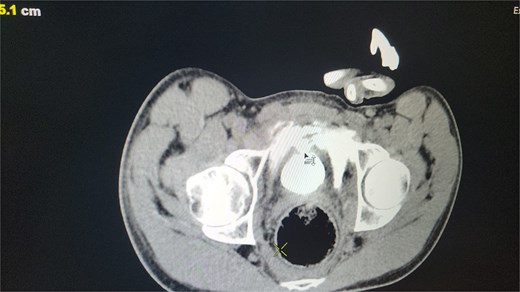

Out of the total cases, four intraperitoneal ruptures (57.1%) and three extraperitoneal ruptures (42.9%) were observed. This highlights the significance of CT cystography in differentiating between these rupture types to inform management strategies (see Fig. 1).

CT scan reveals contrast material leaking from the bladder lumen into the surrounding pelvic cavity, indicating a bladder rupture.

CT cystography proved highly effective for timely and accurate diagnoses, with no reported misdiagnoses or delays. This imaging technique is the gold standard for identifying and classifying bladder ruptures as intraperitoneal or extraperitoneal.